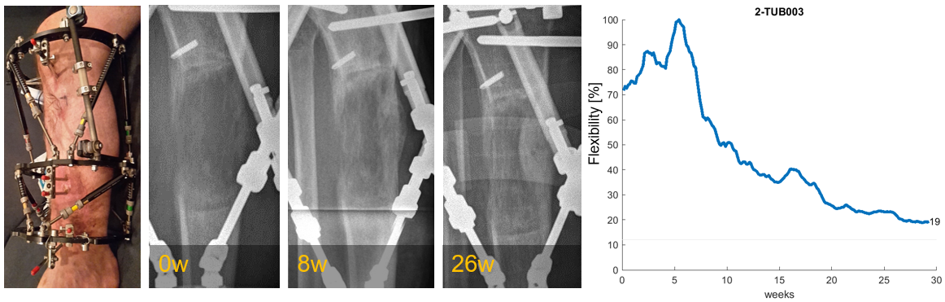

The AO Fracture Monitor is a system developed for continuous in-vivo monitoring of fracture healing (Project 'AO Fracture Monitor') in order to overcome the shortcomings of radiographic methods and instead deliver a reliable, quantitative and timely feedback on healing progression. While the system already delivered preclinical proof of concept, further evidence on its performance and usability in a clinical setting is needed.

AO Fracture Monitor prototypes will be implemented in 10 patients with externally fixated tibia fractures until removal of the fixation hardware at BGU Tübingen, Germany. Healing parameters generated by the device shall reflect the course of healing as observed from clinical and radiological evaluation and thereby strengthen the evidence of the system in a challenging clinical setting.

Clinical data collection is almost completed, with only one patient still left active in the project. Average follow-up time prior to implant removal was 150 days. The external fixator had to be replaced with an intramedullary nail in 3 patients. The monitors provided uninterrupted data flows, with a few exceptions of unintentional device reset, where a manual restart was needed. Despite being hard to determine the loading conditions arising from a hexapod fixator used, the fracture monitor was still able to resolve changes in fracture stiffness throughout the course of healing in most of the cases. Many of the project findings are taken into account for design purposes during the current development of an implantable fracture monitor system.